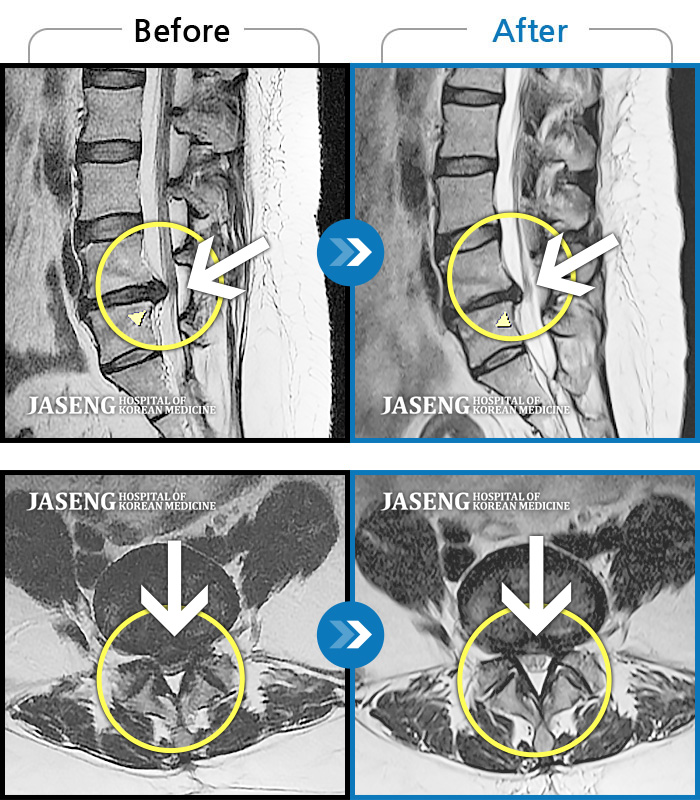

Before

After

환자에게 사전 동의를 받아 동일 조건에서 촬영되었습니다.

개인에 따라 치료 후 부작용이 발생할 수 있으니 의료진과 상담 후 치료를 진행하시기 바랍니다.

좌측 다리 통증이 심하고 다리 감각이 무뎌요.

허리 통증과 심한 좌측 다리 통증